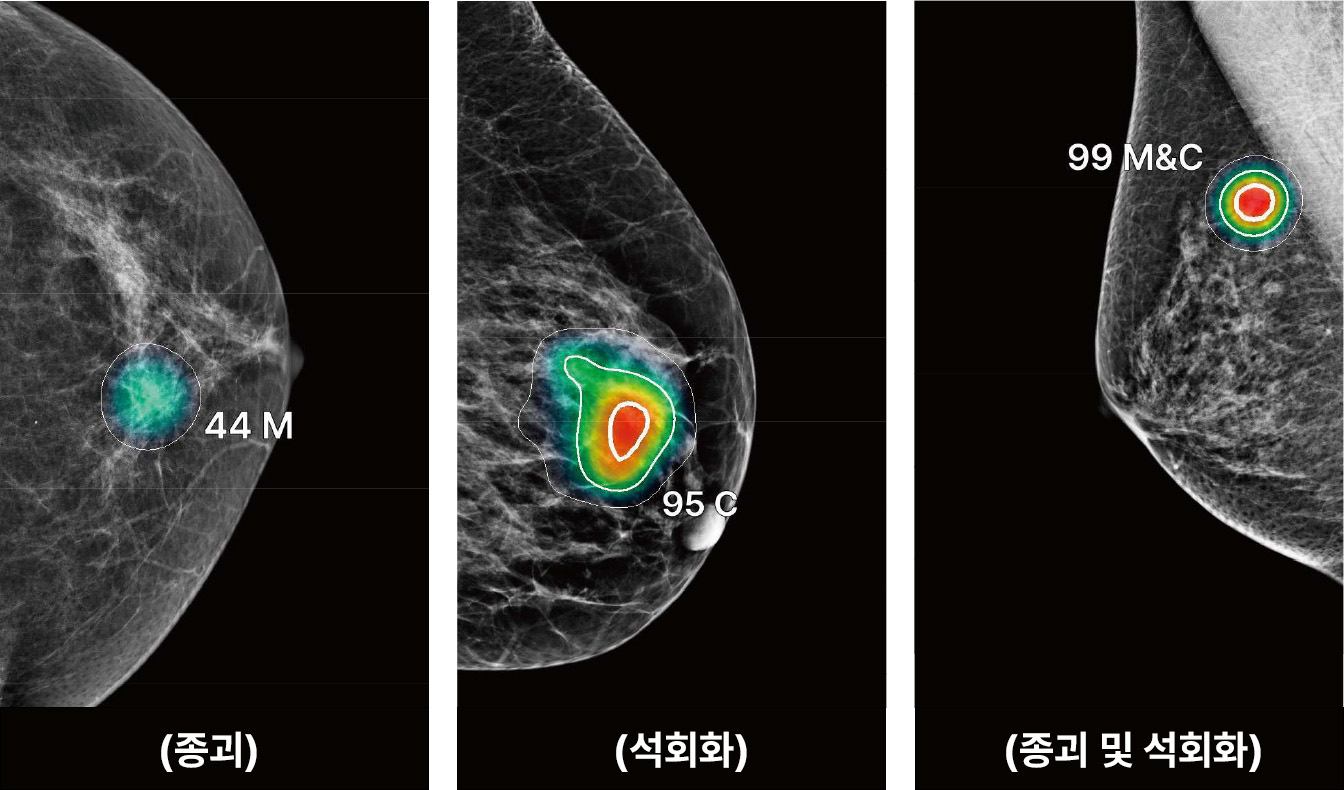

유방촬영술 영상분석 AI솔루션

보이지 않는 조기 유방암, 보조 진단 AI 프로그램으로 정확도 높은 진단이 가능합니다.

Lunit INSIGHT MMG

유방 엑스레이 촬영 영상을 판독 보조하는 의료영상 검출 보조 인공지능 소프트웨어며, 딥 러닝 기반의 인공지능 알고리즘을 적용하여 영상을

자동으로 분석하여 의사의 판독을 보조할 수 있게 하는 의료기기

미세석회화나 작은 종괴 등 육안으로 놓치기 쉬운 병변까지 AI와 함께 확인합니다.